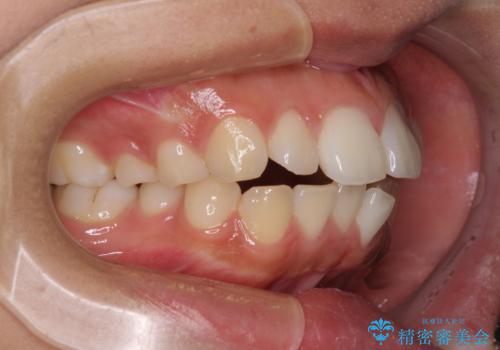

- 出っ歯と口の閉じにくさ、デコボコを気にして来院された患者様です。

口元の突出感を改善するため、上下左右第一小臼歯4本の抜歯を行い、ワイヤー装置による矯正治療を行うこととしました。

舌の突出癖により上下前歯は非接触であり、非常に前方に飛び出している状態でした。

舌のトレーニングをしっかりと行っていただき、口の閉じやすい歯並びに仕上げることができました。